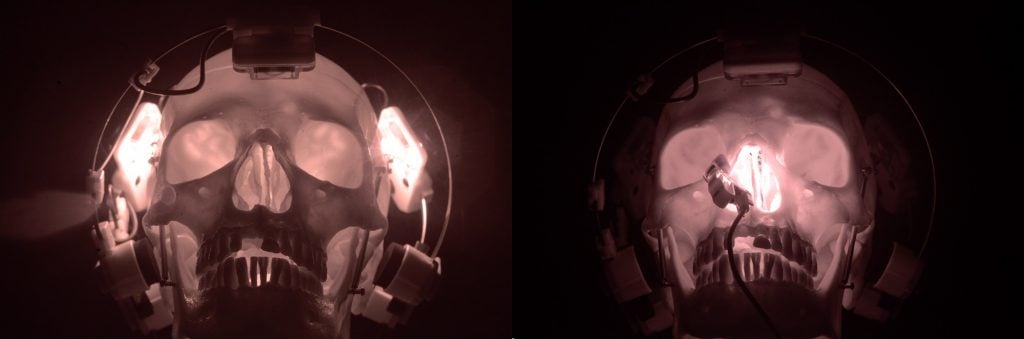

Das Vielight Neuro ist für eine maximale Übertragung der Lichtenergie ausgelegt.

Das Headset der Neuro hat einen angeborenen Designvorteil, da die LED-Module der Neuro so konzipiert wurden, dass sie den Kontakt mit der Kopfhaut maximieren. Die mikrochip-gesteuerten LED-Module kontrollieren auch die Wärmeleistung,

Außerdem ist das Neuro-Headset so konzipiert, dass es sich an verschiedene Kopfgrößen und -formen anpassen lässt. Komfort und Effektivität für Ihr wichtigstes Organ – Ihr Gehirn.

Ein berühmter Küchenchef sagte einmal: “Es ist ganz einfach: Gute Zutaten ergeben ein gutes Essen. Eine weitere wichtige Zutat (oder ein Faktor) bei der Photobiomodulation des Gehirns ist die Art der verwendeten LED-Technologie. Das Vielight Neuro verwendet mikrochip-geregelte LED-Dioden, die die gewünschte Leistung bei vernachlässigbarer Wärme erzeugen. Dadurch können die LEDs in direktem Kontakt mit der Kopfhautoberfläche stehen, um die Energieübertragung und -durchdringung zu maximieren.